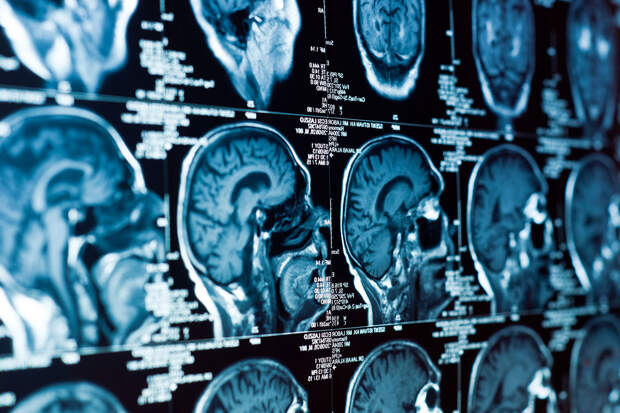

Исследователи из Нидерландского университета неврологии в Амстердаме обнаружили связь между депрессией и иммунной системой мозга. Как оказалось, она менее активна у людей с депрессией. Результаты исследования были опубликованы в журнале Biological Psychiatry.

Однако это оказалось не так. Авторы новой работы изучили образцы мозга, взятые у людей с депрессией после их смерти. Вопреки ожиданиям, клетки микроглии вблизи нейронов демонстрировали пониженную активность, что говорит об отсутствии воспаления.

"Во время исследования мы использовали ткань сразу после смерти, чтобы выделить микроглию, и сравнить ее у людей с депрессией и в контрольной группе. Мы наблюдали аномальную микроглию в первой группе, причем наибольшие отклонения наблюдались у пациентов, которые были наиболее подавлены непосредственно перед смертью", – отметили авторы.

Интересно, что отклонения были замечены только в сером веществе мозга. Это говорит о том, что существует вероятное взаимодействие между микроглией и структурами, расположенными в сером веществе: нейронами и синапсами.